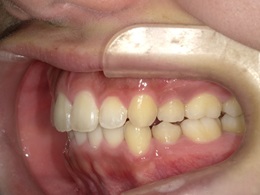

治療後左側

右側治療後